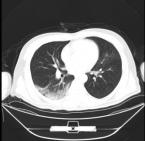

患者因“发热8天”于2020年1月28日入院。患者1月20日开始出现发热,体温最高39.5℃,乏力畏寒,全身酸痛,就诊于外院,行抗病毒治疗。胸部CT示双肺感染,考虑病毒性肺炎。经治疗后,患者仍有发热,且出现活动后气促,以“病毒性肺炎”收入湖北省中西医结合医院隔离病区。入院后西医诊断:新型冠状病毒肺炎(临床诊断)。患者入院后予抗感染、抗病毒、静脉滴注球蛋白等治疗后已无发热,但仍诉活动后气促明显,步行上厕所后即出现气促。于2月5日复查胸部CT提示双肺多发磨玻璃密度感染灶(图2-3-1)。

图2-3-1 2020年2月5日胸部CT